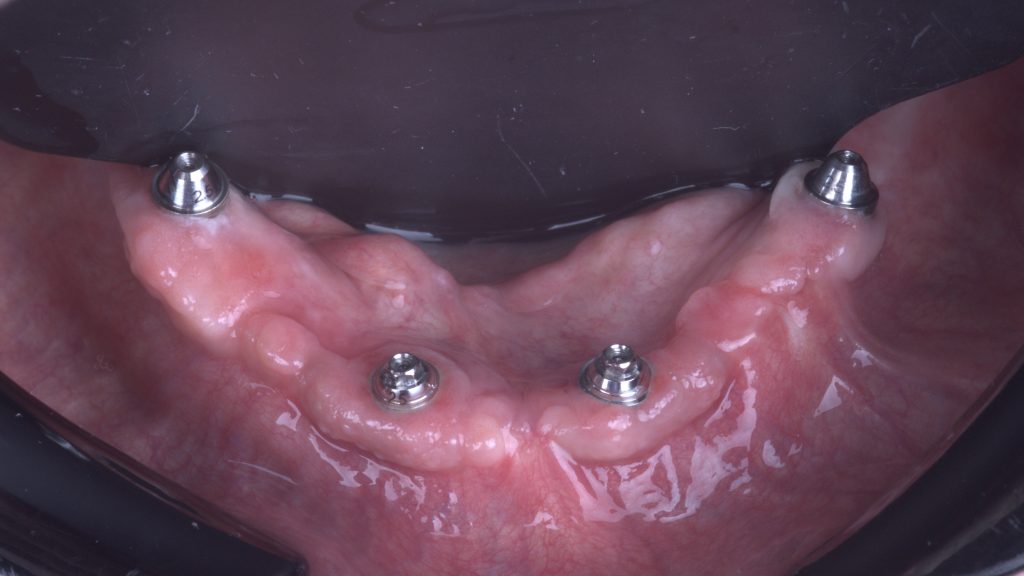

Keratinized tissue

After six months of healing we find healthy keratinized mucosa around implants and restoration

Keratinized peri-implant mucosa

It is a joy to observe perfect soft tissue healing Just look at the robust band of keratinized gingiva